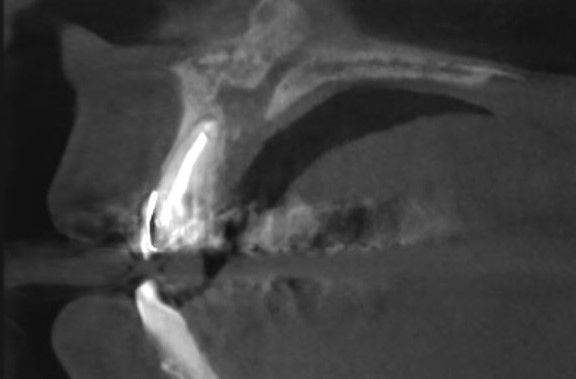

Поперечный срез в области зуба 2.2 - заметно полное закрытие костного дефекта